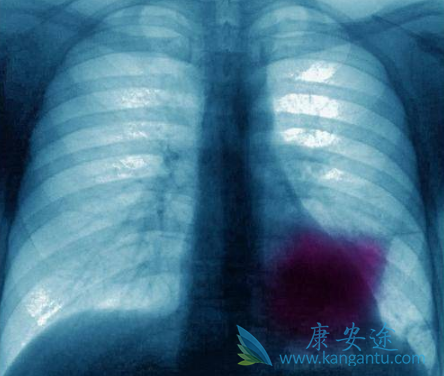

没有基因突变就不会导致癌症,对于癌症的治疗也是基因突变有对应靶向药物的则靶向治疗,没有对应靶点的,则需要使用化疗。对于化疗药物的副作用和疗效与很多基因相关,但并不好判断。近期新发布在《Lung cancer》的文献表明,非鳞非小细胞肺癌患者一线使用的化疗药物培美曲塞和铂的疗效,可以通过ERCC1和ERCC2两个基因的多态性位点来判断,这是怎么回事?

研究者前瞻性地评估了ERCC1、ERCC2、XRCC1和XRCC3的基因多态性,与晚期非鳞非小细胞肺癌接受培美曲塞和铂治疗的疗效的关系。入组了58名患者,均为一线使用培美曲塞联合铂类化疗,检测ERCC1、ERCC2、XRCC1和XRCC3四个参与DNA损伤修复基因的6个多态性位点,以判断这6个位点是否与患者使用化疗的疗效之间有什么相关性。ERCC1基因的8092位碱基的正常情况是(C/C),对化疗有较好的客观反应率,达到了48%,而如果这个位点是变异类型(C/A,A/A),则对化疗的客观应答率就下降至10%。

ERCC1和ERCC2这两个基因的四个多态性位点与较好的总生存期是相关的。ERCC1基因的Asn118Asn和C8092A,ERCC2基因的Lys751Gln和 ERCC2基因的Asp312Asn,病人不会是这4个位点都属于这个情况,总有1-2个是赶上好的(也就是2-3个不好的),则总生存期也是不错的,在30个月左右。如果上面四个比较有利的多态性位点一个也没有出现,都是不利的多态性位点,那么总生存期就下降至11.8个月,差别了近3倍。患者可以此选择化疗方案培美曲塞和铂类化疗时的参考。